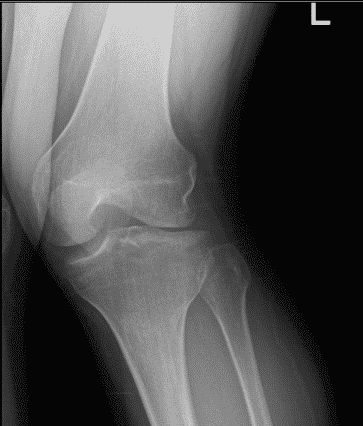

Un paciente de 26 años estaba en nuestra consulta con quejas de dolor en la rodilla izquierda. Le hicieron radiografías de la rodilla izquierda. Como factores agravantes, los pacientes informaron estar de pie, caminar, levantar pesos, girar, empujar/tirar, lanzar, moverse, apoyar peso, hacer ejercicio, cirugías previas, arriba, abajo y por la noche.

El paciente presentó resultados de radiografías que mostraron un leve estrechamiento del espacio del compartimento lateral de las articulaciones. Por lo demás, no tiene nada de especial. La posición es subóptima porque el paciente no puede estirar la rodilla.

Radiografía de rodilla izquierda y radiografía lateral con vistas oblicuas 3